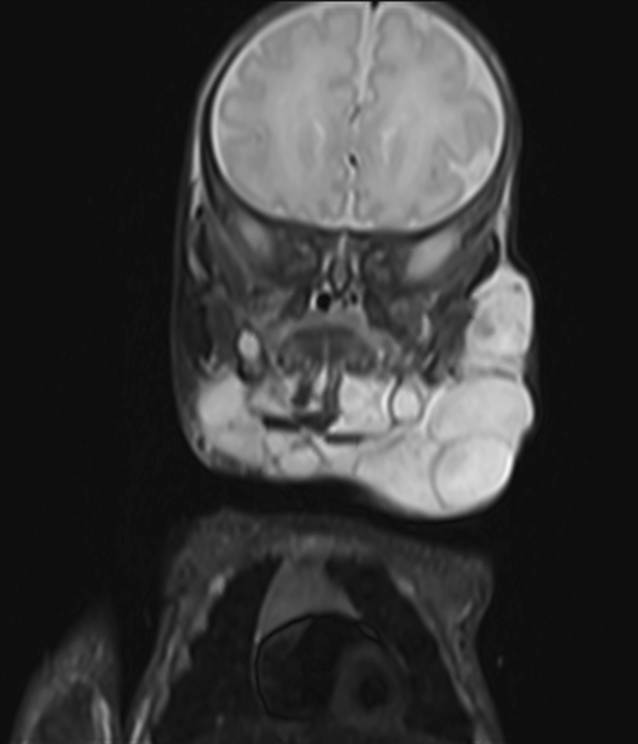

Abb. 2

Patientin 1. Das koronale T2-Magnetresonanztomogramm zeigt eine unscharf begrenzte hyperintense Läsion in der Subkutis und der angrenzenden Muskulatur

Fallbericht 1

Die Erstvorstellung erfolgte wegen einer seit Geburt bestehenden lividen Verfärbung im Bereich des linken Oberschenkels (Abb. 1; Tab. 1). In der klinischen Untersuchung fand sich unter der Haut eine etwa 5 cm große, unscharf begrenzte, derb-knotige Resistenz. Im initialen Blutbild (6. Lebenstag) waren die Thrombozyten normal; vor Behandlungsbeginn waren dreimal diskret erniedrigte Thromboyztenwerte (minimal: 133 G/l) dokumentiert. Die Bestimmung der plasmatischen Gerinnung erfolgte erstmals im 3. Lebensmonat. Es zeigte sich eine leichte Erhöhung des D‑Dimers auf 1,69 mg/l (Normwert: −0,50) bei unauffälliger aktivierter partieller Thromboplastinzeit (aPTT), Prothrombinzeit (PZ), unauffälliger Fibrinogen- und Antithrombin(AT)-Werten. In der Magnetresonanztomografie (MRT) mit Angiografie, die im 2. Lebensmonat durchgeführt wurde, war eine kraniokaudal 7 cm × sagittal 5 cm × axial 1,8 cm messende Infiltration der Subkutis des Oberschenkels ventrolaterodorsal mit fleckigem knotigen Kontrastmittelenhancement und semizirkulärer Infiltration des Musculus rectus femoris und Musculus vastus lateralis sowie Musculus sartorius zu sehen (Abb. 2). Da differenzialdiagnostisch auch ein maligner Weichteiltumor in Betracht gezogen wurde, erfolgte eine Biopsie, deren Ergebnis mit einem kaposiformen Hämangioendotheliom (KHE) vereinbar war. Im Alter von 2,5 Monaten wurde eine Therapie mit Sirolimus (Gesamttagesdosis 0,1 mg/kg und Tag aufgeteilt auf 2 Einzeldosen; Zielspiegel 10–15 ng/ml) begonnen. In den ersten Wochen nach Therapiebeginn wurden deutlich erhöhte Spiegel gemessen, weshalb eine entsprechende Dosisreduktion erfolgte. Im Verlauf konnten dann mit einer sehr niedrigen Sirolimusdosis adäquate Serumspiegel erzielt werden. Allerdings kam es innerhalb von 3 Wochen nach Therapiebeginn zu einer deutlichen Größenzunahme, sodass auch wegen der Gefahr eines Kompartmentsyndroms eine zusätzliche Therapie mit Vincristin (0,025 mg/kg je Einzeldosis) in initial wöchentlichen Abständen eingeleitet wurde. Da die Läsion unter der Therapie kleiner und weicher wurde, konnten die Abstände zwischen den Vincristingaben auf zwei Wochen ausgedehnt und die antiproliferative Therapie nach einer Gesamttherapiedauer von 11 Monaten (19 Vincristingaben) beendet werden. In der MRT-Kontrolle (8. Behandlungsmonat) zeigte sich eine deutliche Befundregredienz. Nachdem sich bei weiteren Kontrolluntersuchungen eine zunehmende Überwärmung der Läsion fand, erfolgte im Alter von 26 Monaten eine neuerliche MRT-Untersuchung. Da die Läsion deutlich an Größe zugenommen und die Ausdehnung der Ausgangsuntersuchung erreicht hatte, musste die Sirolimustherapie wiederaufgenommen werden. Die Therapie wurde während der nun 16 Monate dauernden 2. Therapiephase wegen verschiedener unkomplizierter Infektionen (Varizellen, Harnwegsinfekt, Gingivostomatitis) mehrfach kurzfristig unterbrochen. Daneben wurden gehäuft nicht behandlungspflichtige aphthöse Läsionen im Mundbereich berichtet. Das klinische Leitsymptom der Erkrankungsprogression (Überwärmung) hat sich im Verlauf deutlich gebessert (Abb. 3).